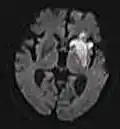

ADC image of the same case of cerebral infarction as seen on DWI in section above

An apparent diffusion coefficient (ADC) image, or an ADC map, is an MRI image that more specifically shows diffusion than conventional DWI, by eliminating the T2 weighting that is otherwise inherent to conventional DWI.[24][25] ADC imaging does so by acquiring multiple conventional DWI images with different amounts of DWI weighting, and the change in signal is proportional to the rate of diffusion. Contrary to DWI images, the standard grayscale of ADC images is to represent a smaller magnitude of diffusion as darker.[23]

Cerebral infarction leads to diffusion restriction, and the difference between images with various DWI weighting will therefore be minor, leading to an ADC image with low signal in the infarcted area.[24] A decreased ADC may be detected minutes after a cerebral infarction.[26] The high signal of infarcted tissue on conventional DWI is a result of its partial T2 weighting.[27]